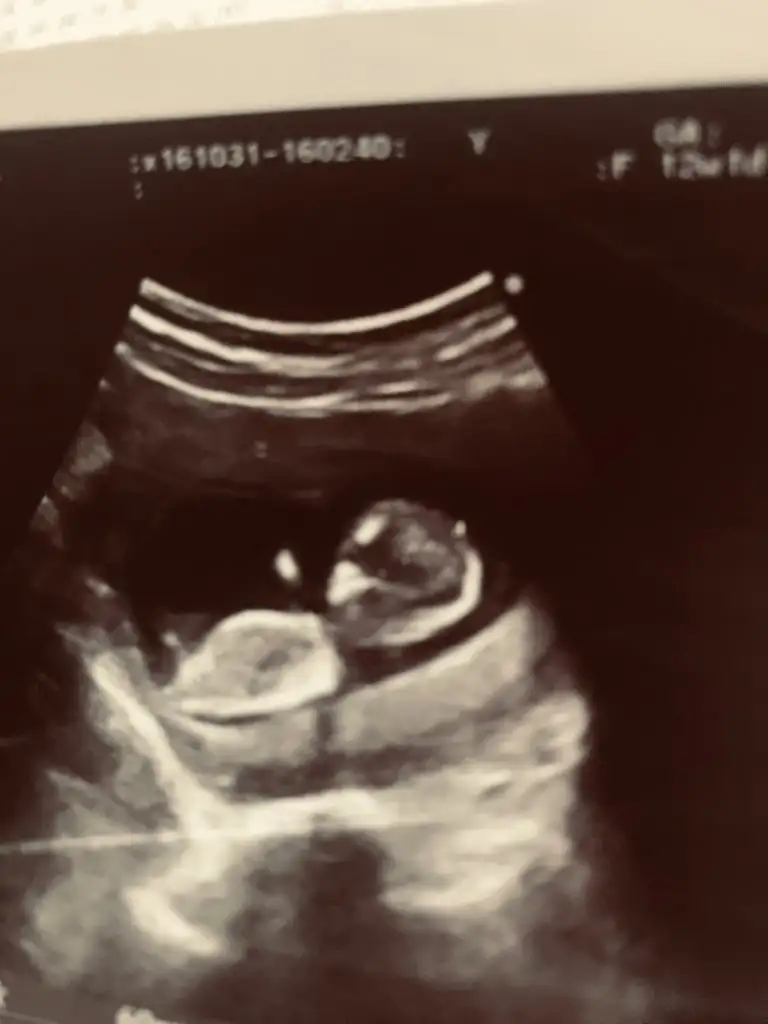

Kız mı dediRica etsem benim bebeğime bakarmısınız iki cinsiyetide söyledi doktorumuz kesinleştiremwdik

İlk kız gibi duruyo ama erkek dedi sonra kıza benziyo dedi 16 da bidaha bakalım dediKız mı dedi

Nubu tam karşıya bakiyor bu durumda % 60 yanılma olur şimdilik kız gibi gibi diyorumÇektim